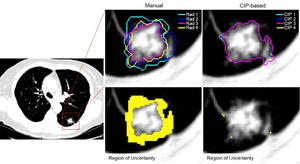

Publication: Cancer Res. 2017 Nov 1;77(21):e104-e107. PMID: 29092951 | PDF Authors: van Griethuysen JJM, Fedorov A, Parmar C, Hosny A, Aucoin N, Narayan V, Beets-Tan RGH, Fillion-Robin JC, Pieper S, Aerts HJWL. Institution: Department of Radiation Oncology, Dana-Farber Cancer Institute, Brigham and Women's Hospital, Harvard Medical School, Boston, MA, USA. Abstract: Radiomics aims to quantify phenotypic characteristics on medical imaging through the use of automated algorithms. Radiomic artificial intelligence (AI) technology, either based on engineered hard-coded algorithms or deep learning methods, can be used to develop noninvasive imaging-based biomarkers. However, lack of standardized algorithm definitions and image processing severely hampers reproducibility and comparability of results. To address this issue, we developed PyRadiomics, a flexible open-source platform capable of extracting a large panel of engineered features from medical images. PyRadiomics is implemented in Python and can be used standalone or using 3D Slicer. Here, we discuss the workflow and architecture of PyRadiomics and demonstrate its application in characterizing lung lesions. Source code, documentation, and examples are publicly available at www.radiomics.io With this platform, we aim to establish a reference standard for radiomic analyses, provide a tested and maintained resource, and to grow the community of radiomic developers addressing critical needs in cancer research. |

A, Overview figure of the process of PyRadiomics. First, medical images are segmented. Second, features are extracted using the PyRadiomics platform, and third, features are analyzed for associations with clinical or biologic factors. B, Stability of radiomics features for variation in manual segmentations by expert radiologists. C, Heatmap showing expression values of radiomics features (rows) of 429 lesions (columns). Note the four subtypes that could be identified from the expression values and their associations with malignancy. D, Area under the curve (AUC) showing the performance of the multivariate biomarker to predict malignancy of nodules. |